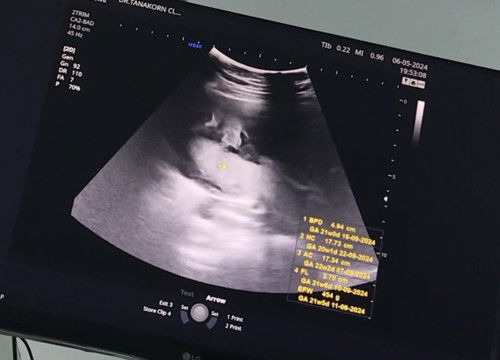

แม่ๆทีมกันยาน้ำหนักลูกกี่กรัมกันบ้างคะ ลูกชายบ้านนี้ 20W4D 454g.ครับบ 👶🏻❤️ #ขอบคุณล่วงหน้าสำหรับความคิดเห็นค่ะ